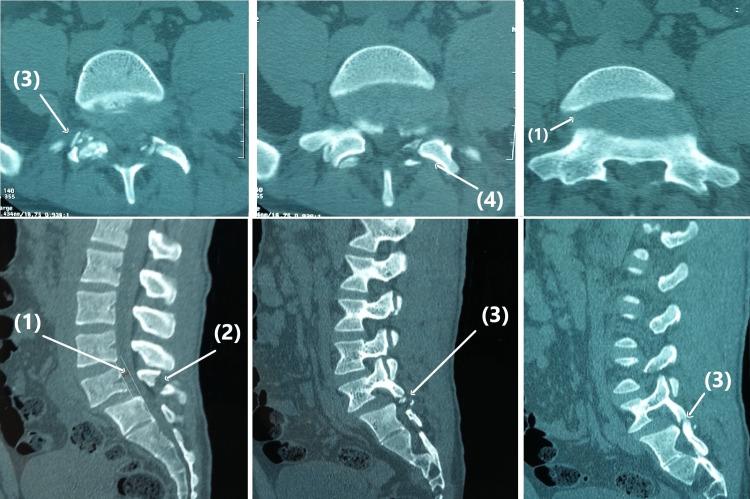

Traumatic dislocation of the lumbosacral joint is a rare and severe lesion usually caused by high-energy trauma. The literature on traumatic spondylolisthesis is limited, and most published papers are sporadic case reports. By presenting the case of an anterior traumatic L5-S1 spondylolisthesis without neurological deficits caused by a 6-meter fall, we discuss the anatomopathological mechanism of this injury, clinical and radiological evaluation, and current management options. The patient was treated surgically with a combined posterior instrumented reduction and transforaminal interbody fusion. At the final follow-up after seven years, the radiological evaluation showed an unchanged spondylolisthesis reduction with reliable fusion healing. In addition, the patient had good functional results and resumed recreational activities and work. Traumatic lumbosacral spondylolisthesis requires a careful and well-documented initial clinical and radiological assessment. Most authors advocate surgical treatment as the mainstay of management. However, the long-term prognosis remains unclear and unpredictable.

腰骶关节创伤性脱位是一种罕见且严重的损伤,通常由高能量创伤引起。关于创伤性腰椎滑脱的文献有限,大多数已发表的论文都是散发性病例报告。通过呈现一例因6米高处坠落导致的无神经功能缺损的前侧创伤性L5-S1腰椎滑脱病例,我们讨论了这种损伤的解剖病理机制、临床和影像学评估以及当前的治疗选择。该患者接受了后路器械辅助复位联合经椎间孔椎间融合的手术治疗。在七年的最终随访中,影像学评估显示腰椎滑脱复位情况未变,融合愈合可靠。此外,患者功能恢复良好,恢复了娱乐活动和工作。创伤性腰骶部腰椎滑脱需要进行仔细且记录完善的初始临床和影像学评估。大多数作者主张手术治疗作为主要的治疗方法。然而,长期预后仍不明确且难以预测。